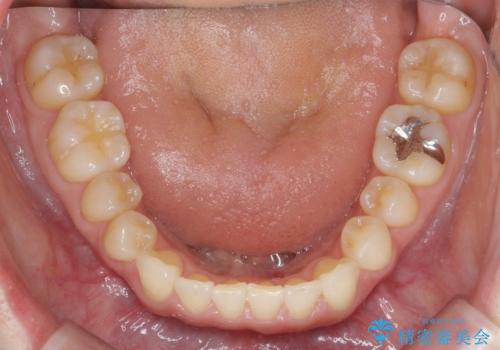

前歯の目立つガタつきをマウスピース矯正で治療

- 大きく傾いてしまった前歯のガタつきの改善を求めて来院されました。

前歯のガタつきをしっかりと取り、機能的・審美的に理想的な歯並びをマウスピース矯正で達成します。

強度のガタつきはマウスピース単体では並び切ることが難しいこともありますが、しっかりと装着していただいたことで良好な治療結果を得ることができました。